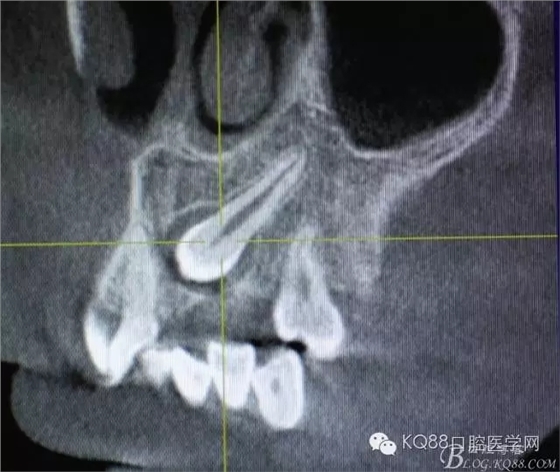

图3.冠向切面:23牙冠紧邻21的牙根